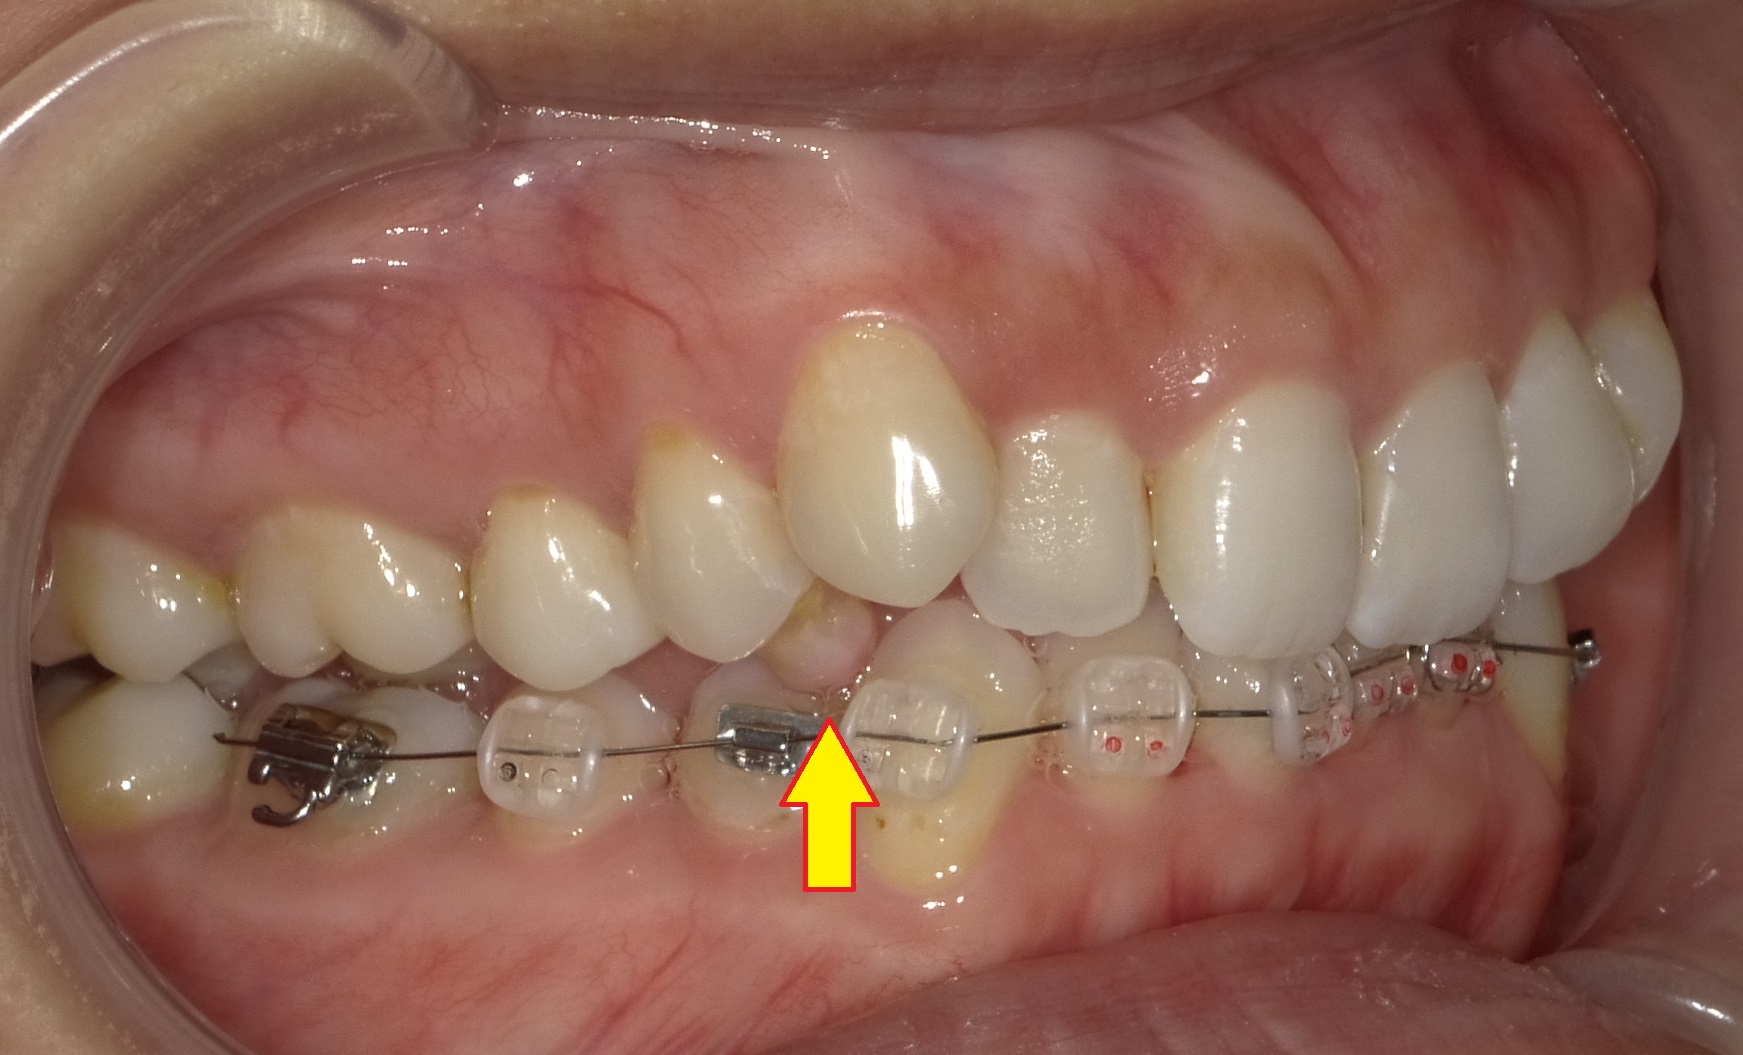

上下矯正器具(今回も上は裏、下は表側から治療を行っていきます)を装着して2週間ほど経過しています。

写真上はまだまだ当然動いてきてるのは分かりませんが、実際は0.8mmほど削った抜く予定の歯の側面のスペースが半分以下に狭まってきているので少しずつ変化はしています。

元々のかみ合わせが深く、噛んだときに下の歯がほとんど見えない状態を改善すべく+単純に矯正器具を着けるために、抜く予定の歯のかみ合わせの面に樹脂製の詰め物をして、「他の歯が全く噛めない状態」にしています。

(上の写真の矢印)

正直いままでの噛み合わせが出来ないどころか、ほぼ物が噛めなくなるので患者さんはすごく大変なのですが、その分下記の効果が期待出来ます。